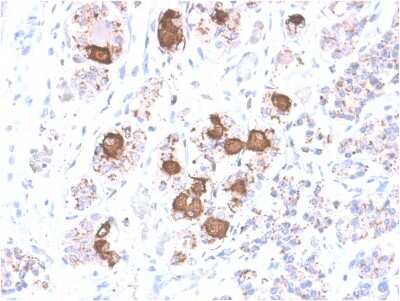

Immunohistochemistry-Paraffin: ACTH Antibody (CLIP/2040R) - Azide and BSA Free [NBP3-08621] - Formalin-fixed, paraffin-embedded human Pituitary stained with ACTH Rabbit Recombinant Monoclonal Antibody (CLIP/2040R).